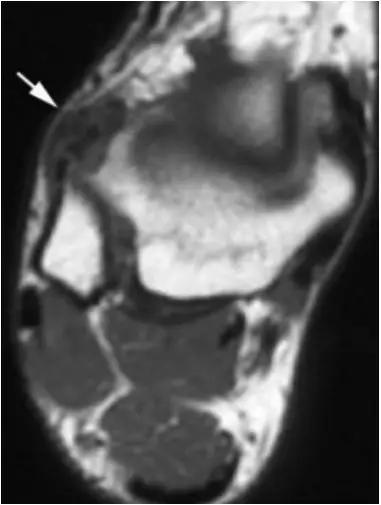

5.后内侧撞击综合症:

影像学表现为距骨胫骨间肌腱及趾长屈肌腱水肿、增厚,内踝及距骨后内侧骨赘形成。

轴位示意图示后内侧撞击综合征:M:内踝;L:外踝;TP:胫后肌腱;FDL:趾长屈肌腱;Talus:距骨。短箭:距骨胫骨间肌腱深层纤维;箭头:距骨胫骨间肌腱后部纤维。

X线平片示胫骨后部骨赘形成,MR质子像黑箭示胫骨内后侧骨赘形成,白箭示内后侧软组织增厚, 白箭头:胫后肌腱;黑箭头:趾长屈肌腱